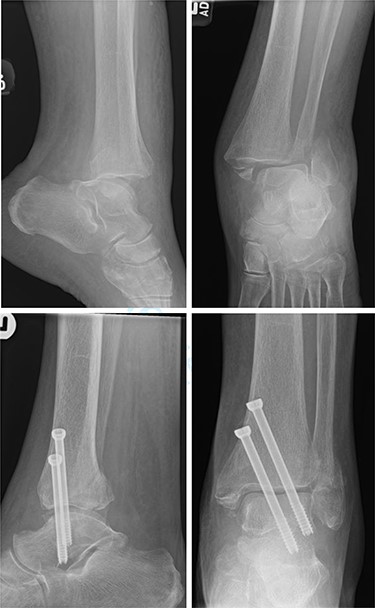

Overall, four out of six patients (66.7%) had satisfactory post-op radiographs with no evidence of talar shift, non/mal-union, widening of the syndesmosis or screw loosening (Figs 1 and 2).

Top—Bimalleolar ankle fracture with talar shift. Bottom—Radiographs at 3 months follow-up showing maintained tibiotalar alignment.